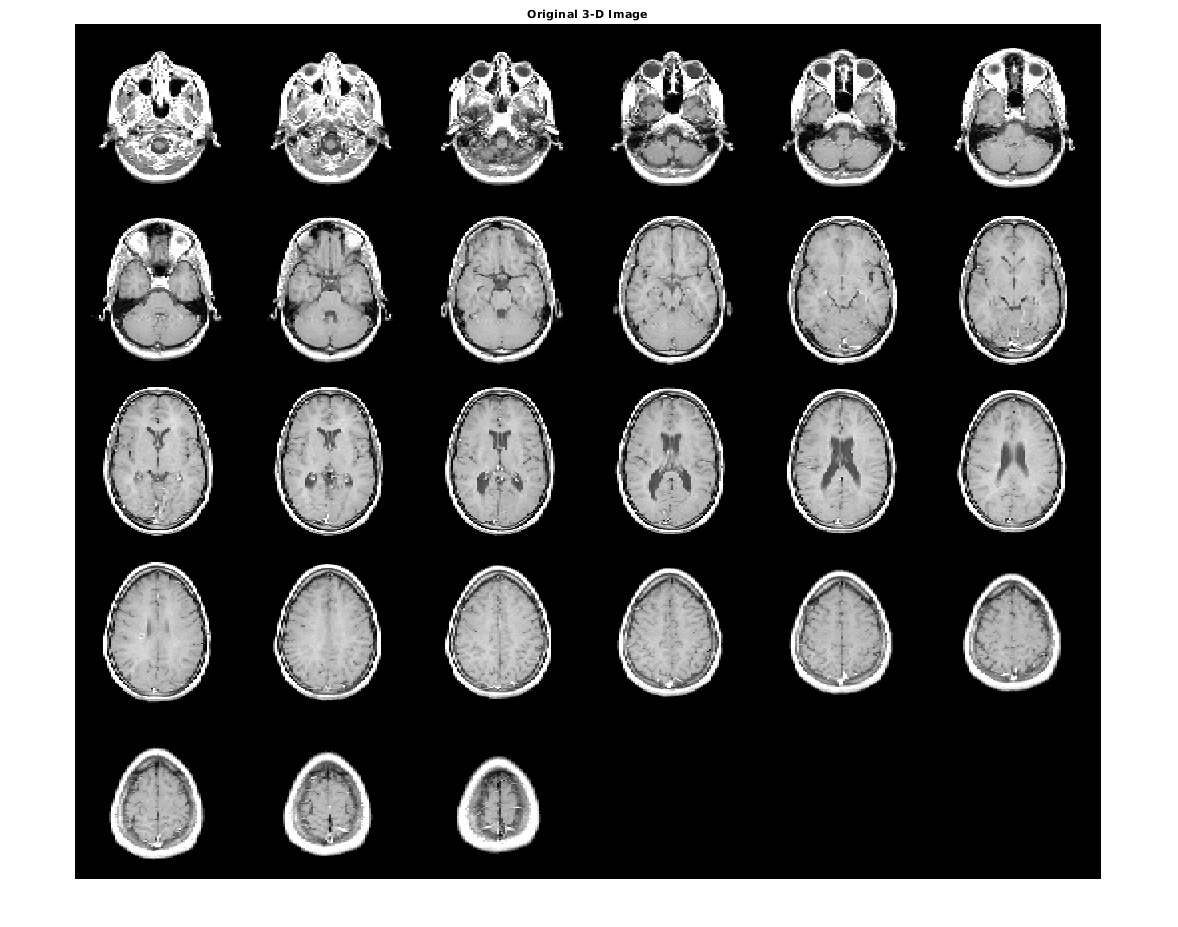

Отобразите исходный объем как срезы.

figure

montage(D,'DisplayRange',[])

title('Original 3-D Image')

Figure contains an axes object. The axes object with title Original 3-D Image contains an object of type image.